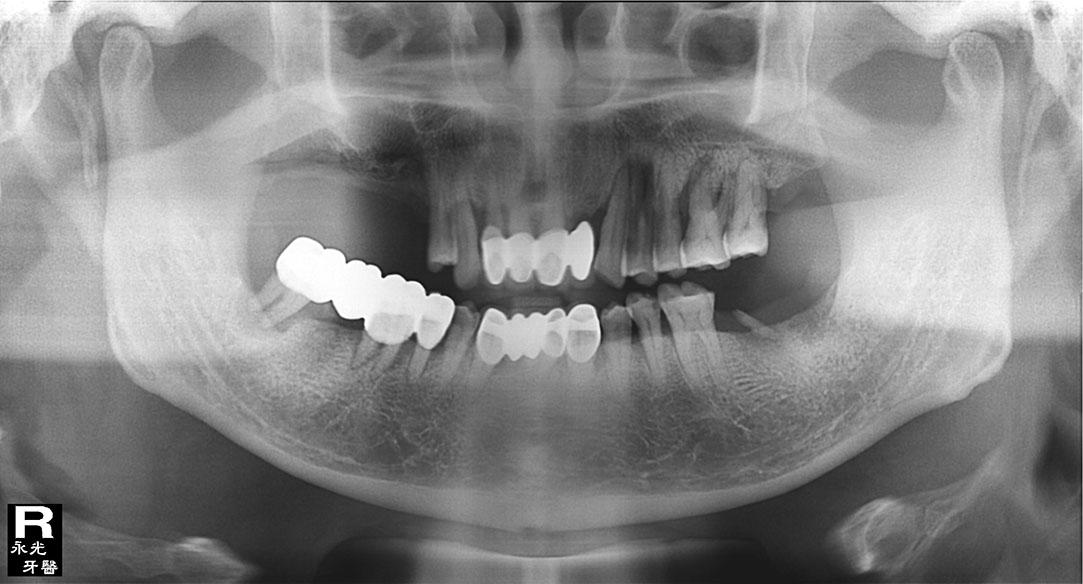

Implant 67d1.jpg

光牙醫